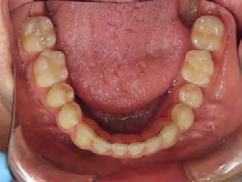

4). Archwires were upgraded incrementally into 19 x 25 SS. Once the bite was completely closed, the patient was referred to the myofunctional therapist to begin treatment. Eight sessions of myofunctional exercises were performed, focusing on muscle building, toning, synchronicity and awareness. Improvement in correct chewing, swallowing and resting postures of the lip and tongue were addressed. All appliances were removed 21 months after initial insertion (Figure 5), and the patient was referred to a re-

storative dentist for veneers on the maxillary central incisors; the patient opted for gold veneers (Figure 6). Clear removable retainers were inserted with a fixed mandibular retainer canine-to-canine.

The patient finished with Class I occlusion, ideal overbite and overjet. The arches are co-

Figure 5. Final records.

ordinated, lateral open bite closed and occlusal cants leveled. From the frontal cephalometric tracings, maxillary width increased from 58 mm to 69 mm. From the lateral cephalometric tracing, the incisor angulations remained unchanged. The final report from the myofunctional therapist indicated the patient eliminated the bilateral posterior tongue-thrust swallowing pattern with saliva, liquid and solid swallows. Correct swallowing mechanics were demonstrated while sipping/gulping liquids from a cup. His day and nighttime tongue-resting postures were reported to be on his incisive papilla, with lateral margins lightly suctioned into the upper arch. Lips were closed and competent diurnally and nocturnally.

Most recent records are two years after removal of the orthodontic appliances, demonstrating the stability of the results (Figure 7).